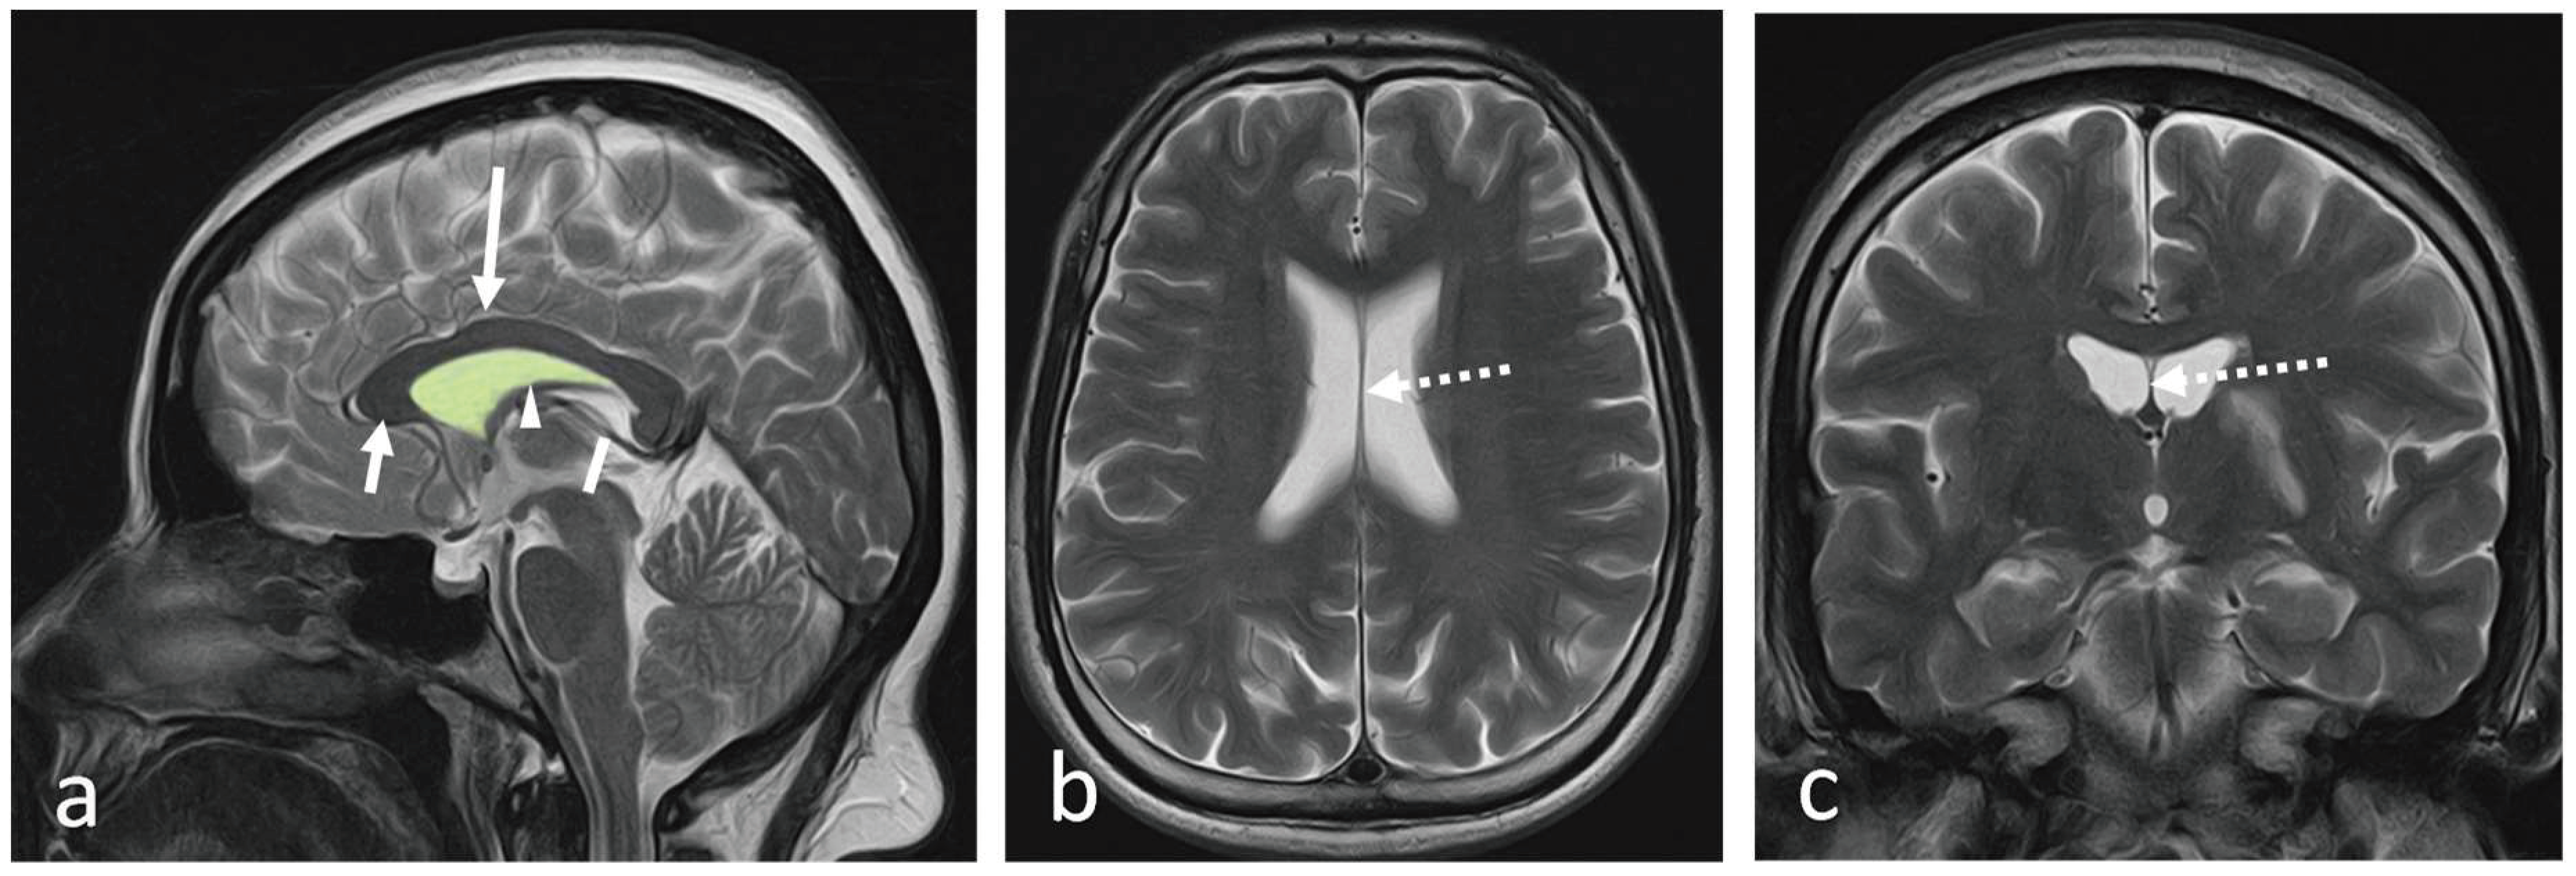

Anatomical variations and clinical significance have been described in the literature. There are three types of variations of SP exits naming cavum septum pellucidum (CSP), cavum vergae (CV) and cavum veli interpositi (CVI) (Figure 2 and Figure 3). The objective of this article is to describe the gross and radiological anatomy of these variations and the clinical implications of variations.

CV has the following boundaries: anteriorly; the anterior limb of the fornix, superiorly; the body of the corpus callosum, posteriorly; the splenium of the corpus callosum, inferiorly; the hippocampal commissure (5).They demonstrated a concurrent prevalence of around 21.1% for CSP and CV in healthy adults using an MRI brain study and isolated CV in 4 % of subjects. Nakano et al. found that the average prevalence of CV alone in 1,050 children was 0.4% using CT brains (8). However, Schwidde et al. did not find CV alone in any of the 1,032 CT brains they examined(9). When associated with CSP, the CV is collectively known as the cavum septum pellucidum et vergae (CSPV) (Figure 4a-c).

The velum interpositum space is a triangular shape midline potential space, and when this space is expanded, it is called CVI (Figure 5a-c).

Figure 2a and Figure 2b. Sagittal and coronal line diagrams show the locations of the CSP (green), CV (dark blue), and CVI (red) in relation to the lateral (light blue), third (3) and fourth (4) ventricles. Case courtesy of Gaillard F, Ventricles with cava. Case study, Radiopaedia.org. https://doi.org/10.53347/rID-35909.